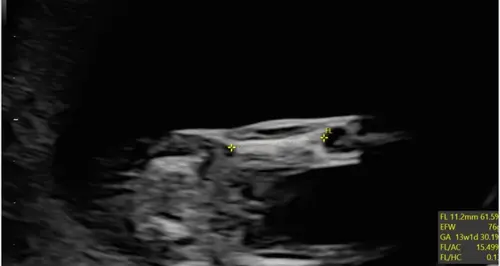

Ik heb gisteren een geslachtsecho gehad met 16 weken, het is een jongetje alleen heb ik het gevoel dat het aanzicht vanaf de bovenzijde is? Klopt dit?😋

Nee dit is onder het kontje zicht, dit is zeker weten een jongen😊